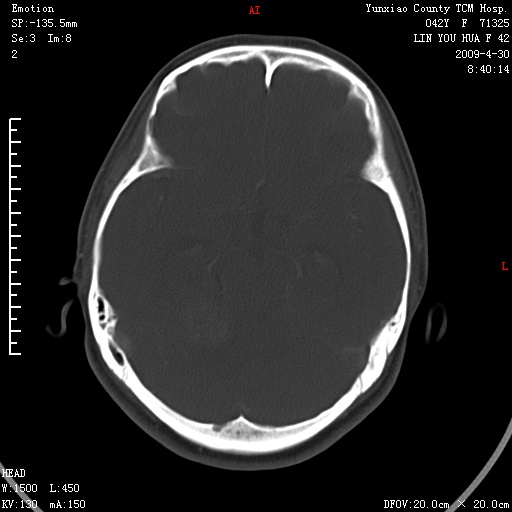

1)右侧听神经瘤。2)阻塞性脑积水。